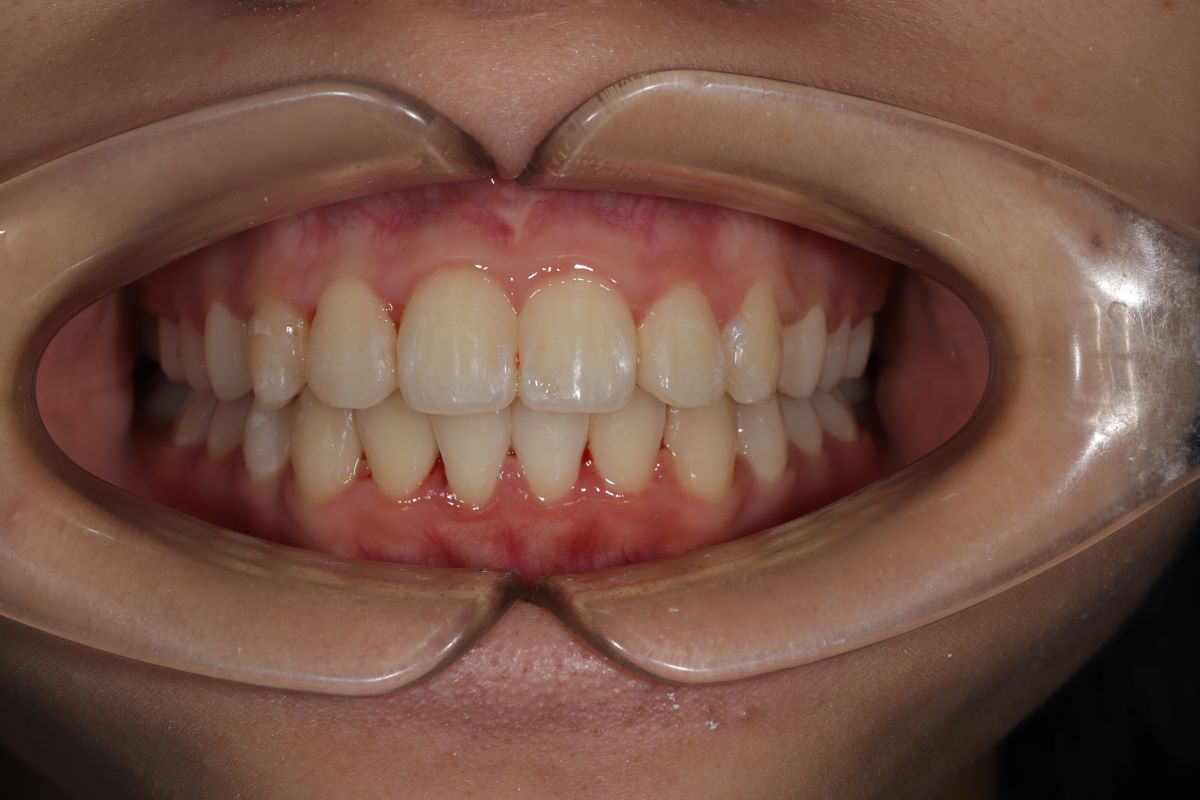

4 Kết quả sau niềng - Màn "lột xác" ấn tượng

- Sau khi tháo niềng, Diệp Anh thay đổi rõ rệt:

- Răng thẳng hàng, không còn chen chúc

- Khớp cắn chuẩn – ăn nhai tự nhiên

- Khuôn mặt cân đối, góc nghiêng hài hòa hơn

- Nụ cười rạng rỡ – tự tin trong giao tiếp, chụp ảnh